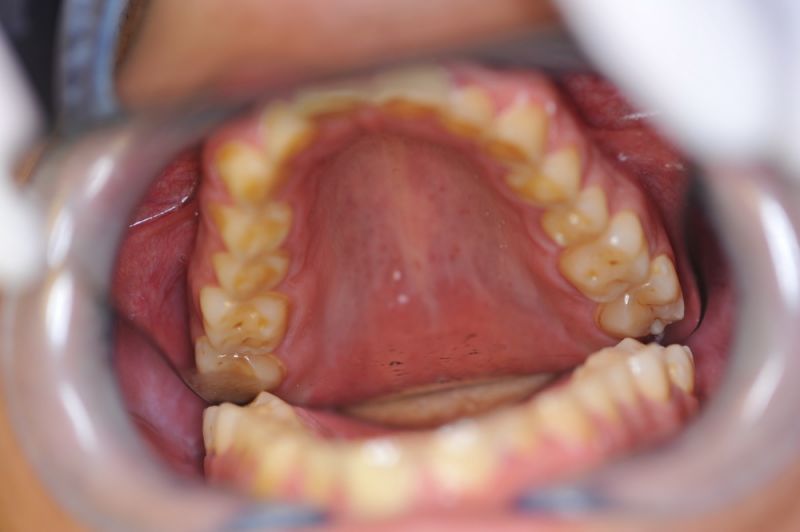

In dem Fall ist noch Optimierungspotential, was die Verschlüsselung der Seitenzähne betrifft. Gemessen an der Ausgangssituation ist das Ergebnis sehr gut und die Versorgung mit Laborgefertigten Dauerprovisorien lässt eine Beruhigung der gesamten Situation zu.

Auch in diesem Fall zeigt sich einmal mehr, dass der "Umweg" über Laborgefertigte Dauerprovisorien zur Einstellung einer neuromuskulär zentrierten Bisslage immer ein guter Weg ist.